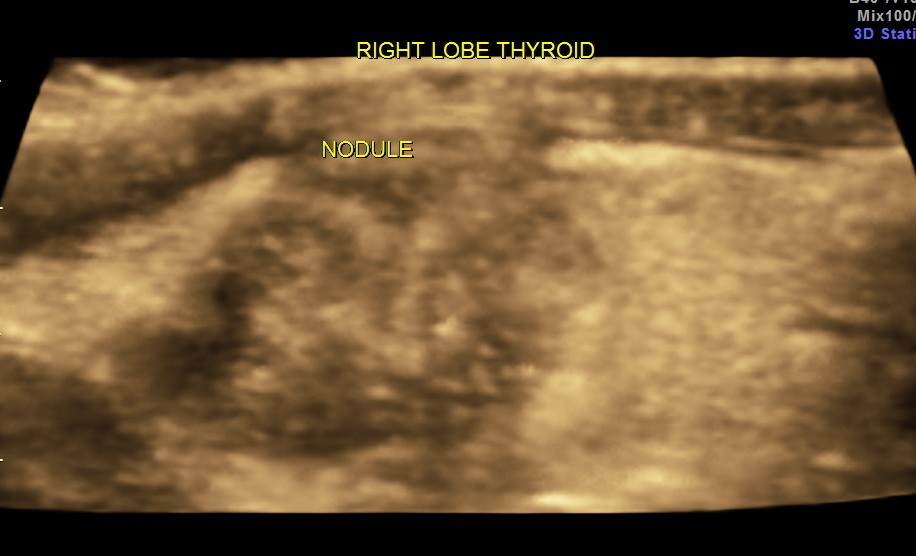

This was a 40 year old lady evaluated for a palpable neck mass on the right side.

Ultrasound revealed he following .

The right lobe of the thyroid revealed an irregular mass , with indistinct margins , punctate calcification and vascularity within and around the nodule.

The 3 D reconstruction images very clearly show the indistinct and irregular margins and the punctate calcification.